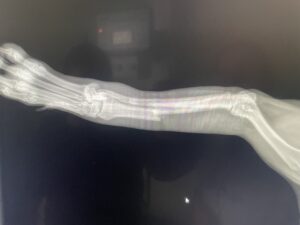

Sierra’s broken leg